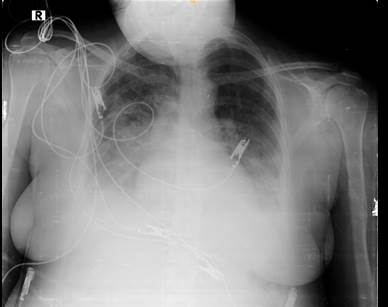

Radiografía de Tórax

Imagen N° 1

01 de Enero de 2024

Presencia de líquido en los espacios extravasculares del pulmón (intersticial y alveolar) en cantidad superior a la fisiológica, en fase alveolar por coalescencia predominante en el tercio interno del pulmón, con patrón en " alas de mariposa"

Dentro de exámenes de imagen, uno que puedo ayudar a contribuir a observar el desarrollo de la enfermedad es la radiografía de tórax con hallazgos como: lineas Kerley B e infiltrados pulmonares. En la gasometría evidenciamos disminución de PaO2, el electrocardiograma y ecocardiograma puede ayudar a establecer el diagnóstico y tratamiento. (Ware LB, 2005) El péptido natriurético tipo B (proBnp) no es utilizado como marcador sérico en mujeres embarazadas a diferencia de su amplio uso en las mujeres que no la están. (Kindermann M, 2008) (Peacock F, 2011).